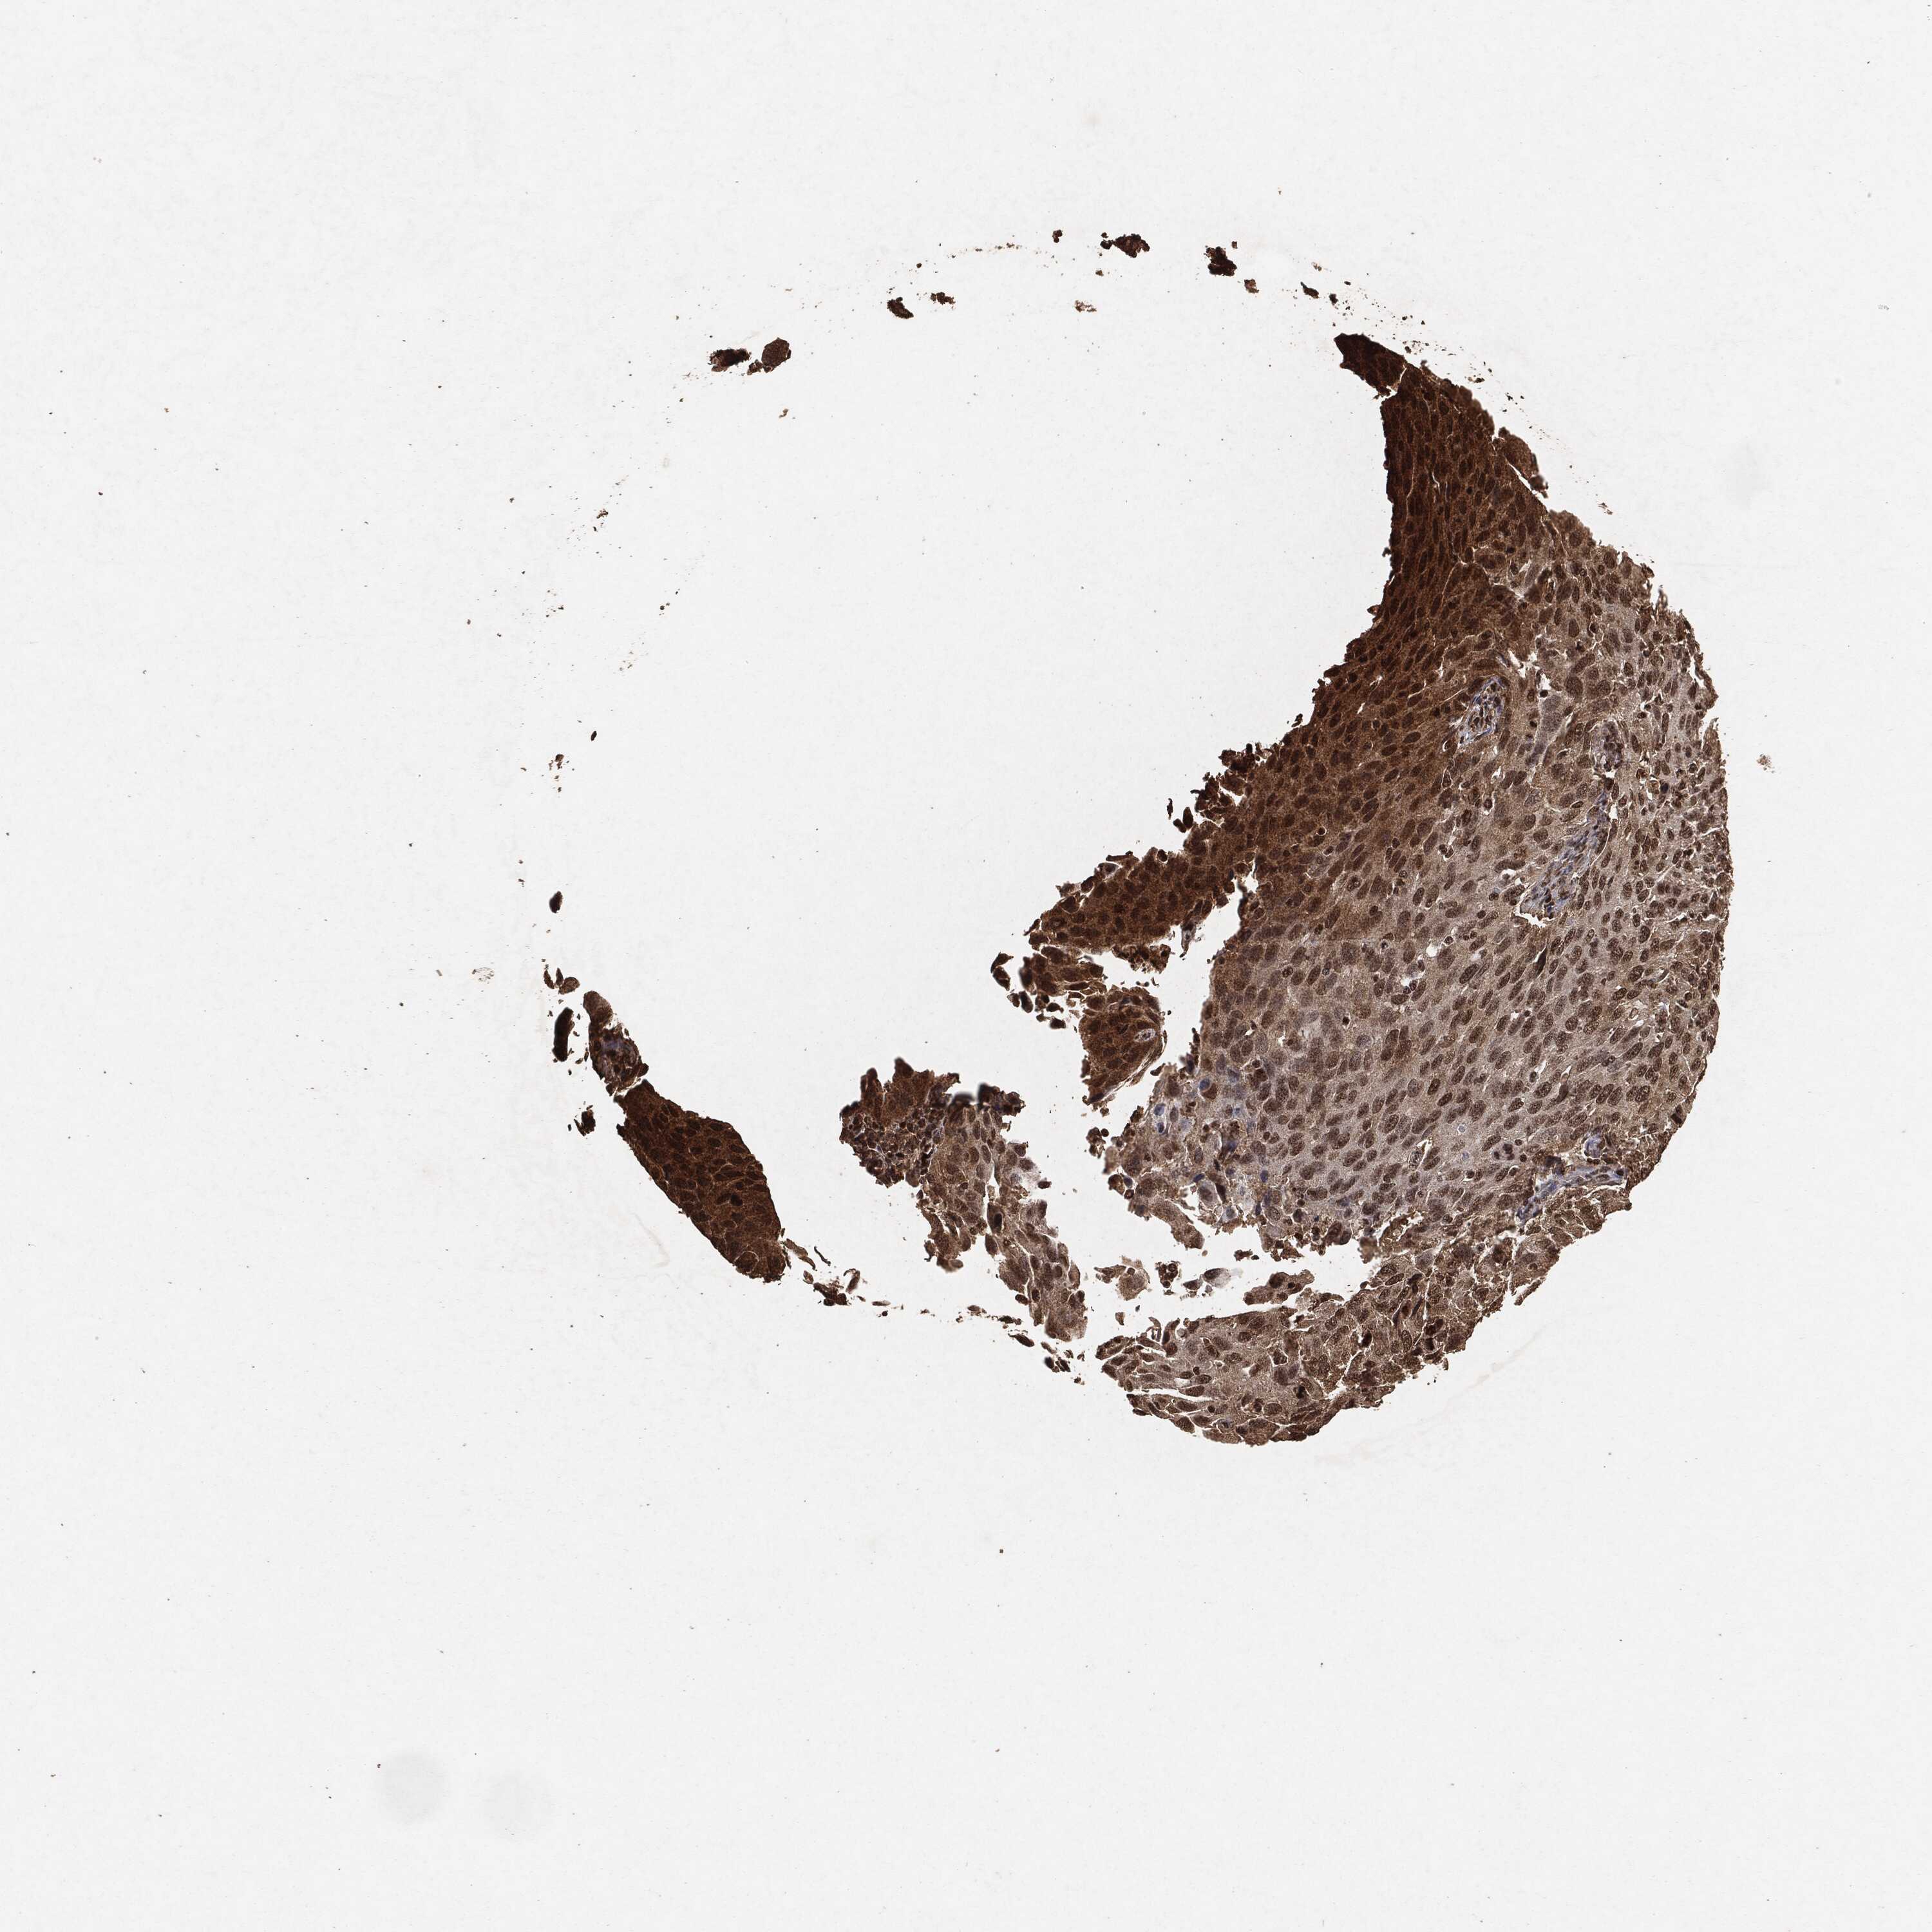

CERVICAL CANCER - Protein expressioni

A mouse-over function shows sample information and annotation data. Click on an image to view it in a full screen mode. Samples can be filtered based on level of antibody staining by selecting one or several of the following categories: high, medium, low and not detected. The assay and annotation is described here.

Note that samples used for immunohistochemistry by the Human Protein Atlas do not correspond to samples in the TCGA dataset.

Antibody stainingi

Antibody staining in the annotated cell types in the current human tissue is reported as not detected, low, medium, or high, based on conventional immunohistochemistry profiling in selected tissues. This score is based on the combination of the staining intensity and fraction of stained cells.

Each image is clickable and will lead to virtual microscopy that enables deeper exploration of all samples and also displays staining intensity scores, fraction scores and subcellular localization as well as patient and tissue information for each sample.